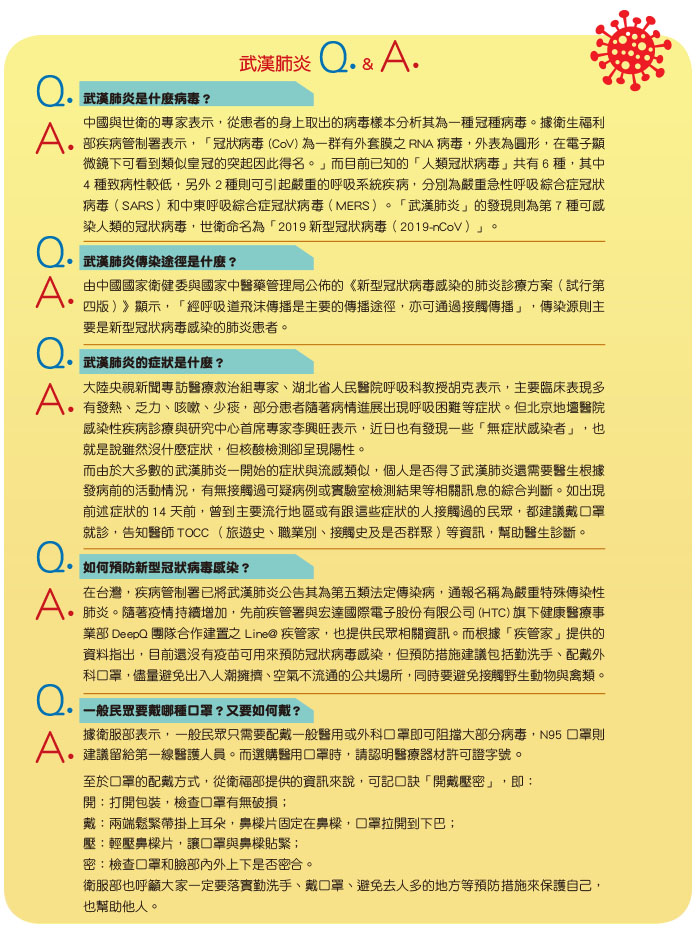

2019年12月底,中國湖北省武漢市華南海鮮市場一帶出現「不明原因肺炎」,隨後疫情不斷升高,引發國際關注。2020年1月12日世界衛生組織確認是新型冠狀病毒株引起的肺炎,為避免用以地名稱呼病毒而有汙名化的嫌疑,世衛將「武漢肺炎」正式命名為「2019新型冠狀病毒(2019-nCoV)」。

據了解SARS及MERS都是蝙蝠傳染給動物再傳給人,而引發武漢肺炎的「2019新型冠狀病毒(2019–nCoV)」,目前公認也是蝙蝠先傳給動物再傳給人,但目前為止傳給哪一種動物還不知道,醫界普遍認為如果能及早確認成為感染源的動物,切斷它與人接觸的管道,對控制疫情也有幫助。

傳播者

大陸國家衛健委高級別專家組組長、中國工程院院士、著名呼吸病學專家鍾南山表示,從病毒的傳播規律來看,呼吸道感染是重要管道,比如飛沫傳染、接觸傳染,目前新型病毒沒有有效的針對性藥物,只能把病人做很好的隔離,不要讓他們與健康的人接觸,這是是疫情防控最有效的方法。「如果能控制住,不任疫情發展,我們就不會出現SARS的情況。」

破關技

17年前的SARS瘟疫,仍留下許多的不解之謎,但我們至少得知,SARS爆發期間,香港公衛團隊分析染病和未染病的醫護同仁,發現戴口罩、手套、常洗手、穿長袍能有效保護醫護同仁,上述四種保護措施全數採用的69名同人皆未受感染,而受感染的同仁至少缺乏一項保護措施,顯示阻擋飛沫傳染的措施能保護人體。

- 《獨家報導》關心您

防範武漢肺炎,出門戴口罩、用肥皂勤洗手、少去人多的場所、避免食用生肉及生蛋、避免接觸禽畜類動物! - 回國若身體不適請主動通報,14天內出現疑似症狀請先撥打防疫專線,並戴上口罩儘速就醫,務必告知醫師旅遊史。

※免付費防疫專線:1922、0800-001922

※加入Line的「 疾管家 」,即可透過AI互動功能,快速了也武漢肺炎之疾病介紹、預防方法、回國民眾注意事項、國際疫情等諮詢功能。